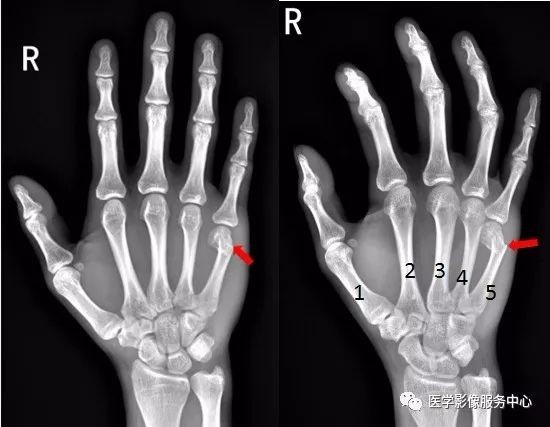

右手骨折 手術- 橈骨遠位端骨折は骨折の中でも、比較的多く見られる骨折です。 しかし、「橈骨遠位端骨折とうこつえんいたんこっせつ」と聞いてもピンとこない方がほとんどだと思います。 では、橈骨とはどこの骨で、どんな骨折なのでしょうか? 上の骨折部位 1.中手骨骨幹部 (こっかんぶ) 骨折 原因: 中手骨の中央部を骨幹部といい、この部での骨折です。 物が手の甲に当たるなど、強い力が直接骨に加わったり、手をひねる力が加わったりして発生します(図2、3)。 症状:

手首の骨折の治療法 手首の骨折の治療は、自然治癒力によって癒合させるのが基本です。 応急処置 応急処置は症状の悪化を防ぎます。骨折部がズレると治療行程が増えて、治療期間が長引きます。 まずは副木で手首の関節を固定します。 良いほうの右手の骨と比べて見ても、 ほぼ変わりないくらい骨折部分がきれいに治っていることがわかります。 この時点で、しっかり治ったことを確認して、 通院終了となりました。骨折部位によって骨の転位方向が変わります。 a, 基部:浅指屈筋腱付着部よりも 近位 で折れた場合は 屈曲変形(背側凸) が起こりやすく(図41) b, 中央:浅指屈筋腱付着部よりも 遠位 で折れた場合は 伸展変形(掌側凸) の変形になりやすい(図42) c, 遠位:受傷機転により変形方向が